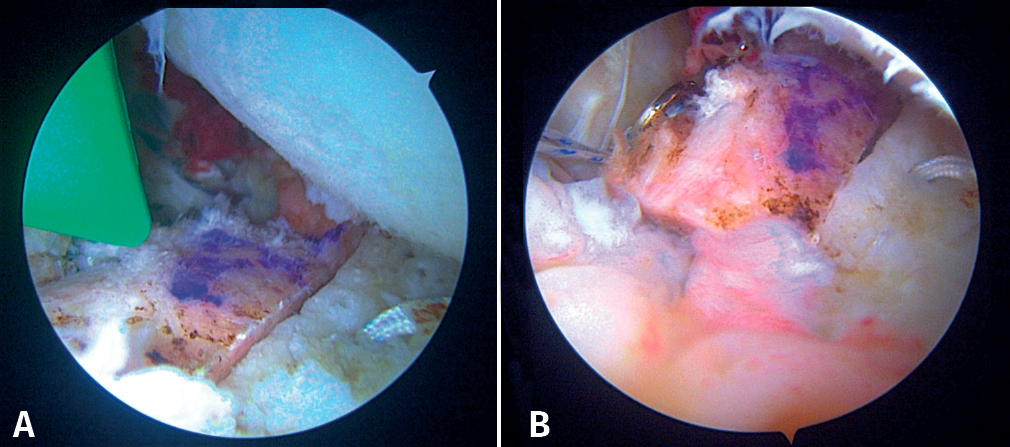

During this time, a second surgeon prepares the graft, giving it a rectangular shape and a size of 20 × 10 × 10 mm. To do so, he/she uses the instruments of the Glenoid Bone Loss® system (Smith & Nephew), drilling two holes with a 2.8 mm drill and spaced 10 mm apart, assisted by the specific graft preparation forceps (Figure 4A).

On the preparation table, one suture of the upper loop is passed through the upper orifice of the bone block and the lower loop through the lower orifice. These two suture loops are then used to close the double EndoButton® (Smith & Nephew) and thread the implant through each orifice of the block. Tightening is applied until both buttons are seated on the free surface of the bone block (Figure 4B).